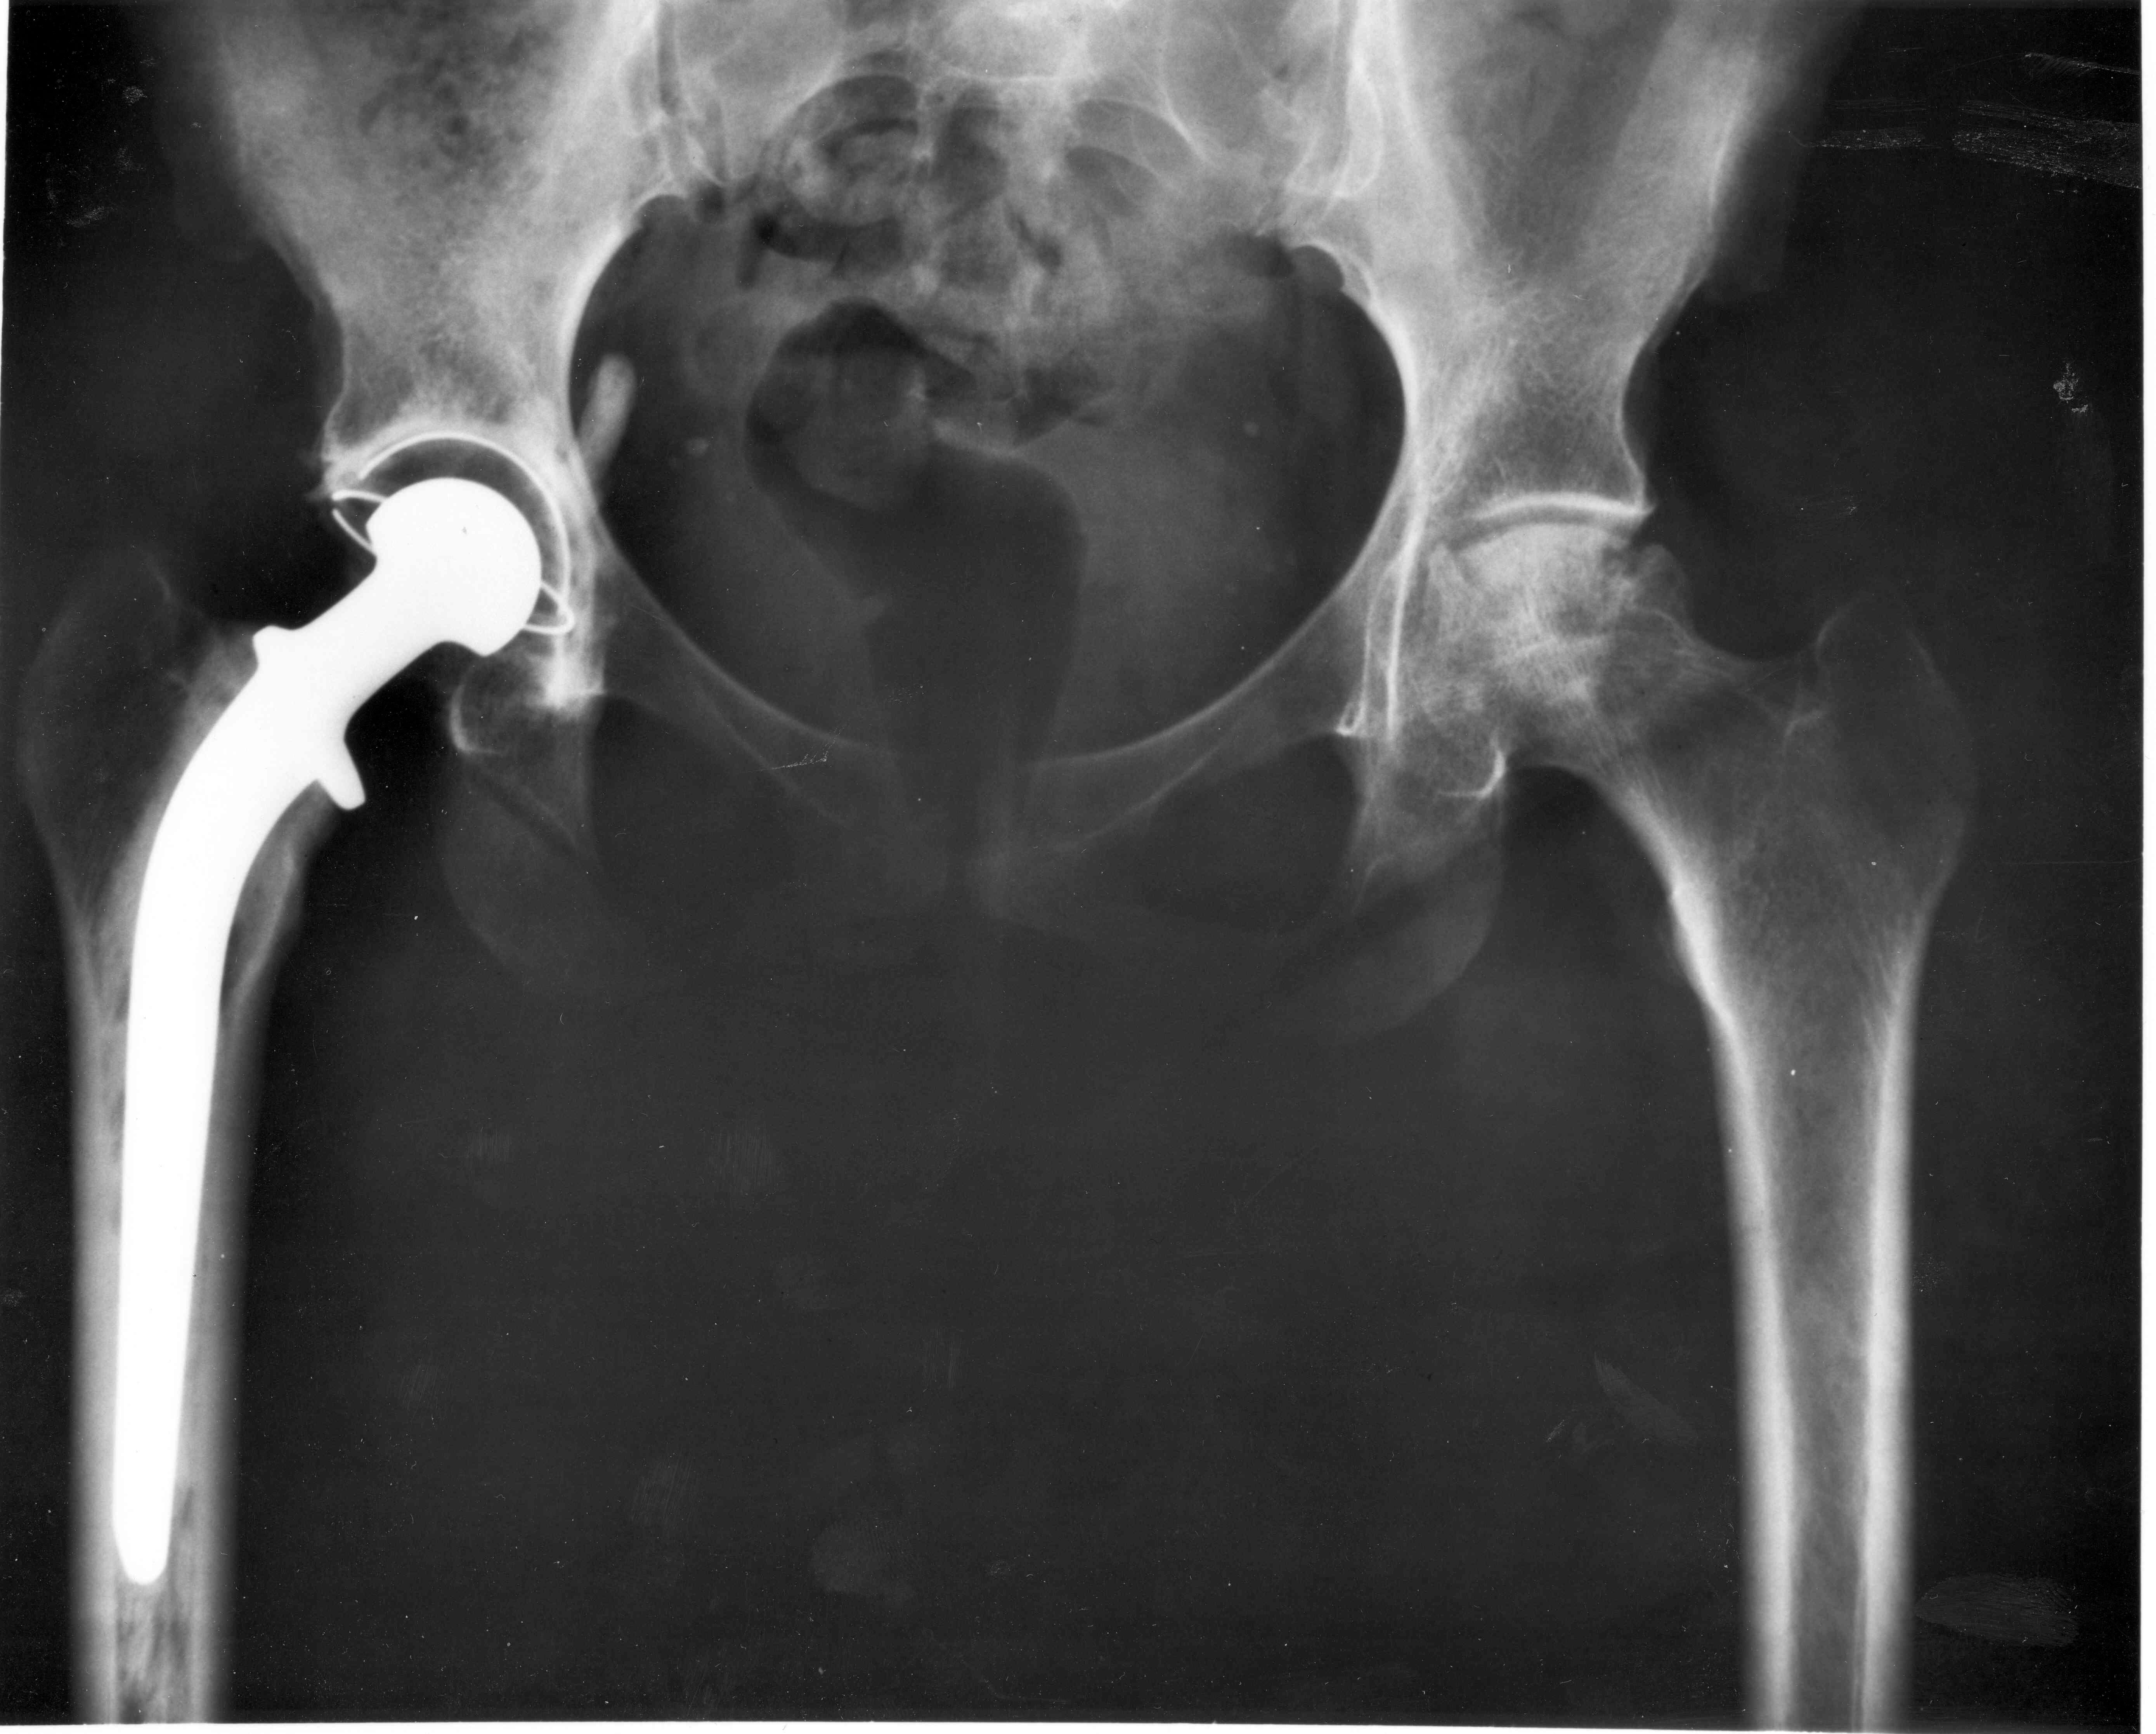

O veterinário será responsável por avaliar as articulações do quadril e fará radiografias na área da pelve para identificar o problema. Uma vez diagnosticada, há diferentes tratamentos para aliviar os sintomas e evitar o progresso da doença.

O tratamento pode incluir fisioterapia, restrição de atividades, uso de anti-inflamatórios orais ou injetáveis e controle do peso. Além disso, em casos mais avançados, pode ser preciso fazer uma cirurgia que pode até incluir uma artroplastia total do quadril.